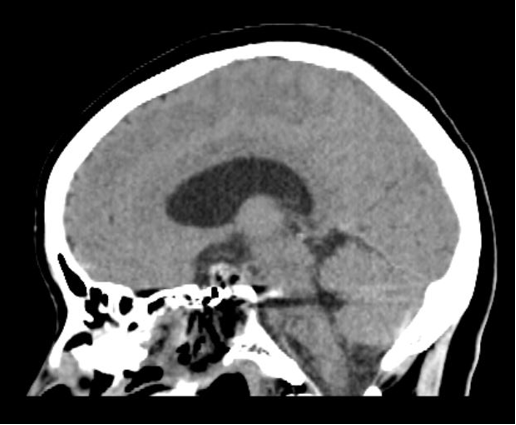

术前头部CT,提示鞍区肿瘤,累及鞍内鞍上